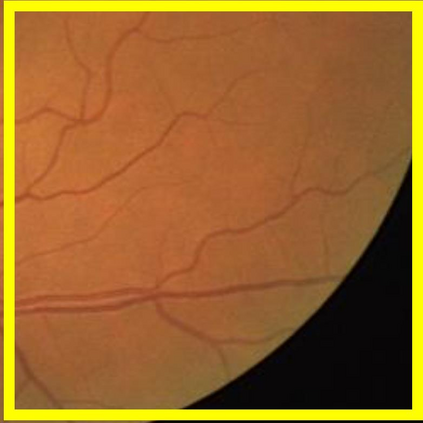

Blood vessel segmentation is crucial for many diagnostic and research applications. In recent years, CNN-based models have leaded to breakthroughs in the task of segmentation, however, such methods usually lose high-frequency information like object boundaries and subtle structures, which are vital to vessel segmentation. To tackle this issue, we propose Boundary Enhancement and Feature Denoising (BEFD) module to facilitate the network ability of extracting boundary information in semantic segmentation, which can be integrated into arbitrary encoder-decoder architecture in an end-to-end way. By introducing Sobel edge detector, the network is able to acquire additional edge prior, thus enhancing boundary in an unsupervised manner for medical image segmentation. In addition, we also utilize a denoising block to reduce the noise hidden in the low-level features. Experimental results on retinal vessel dataset and angiocarpy dataset demonstrate the superior performance of the new BEFD module.